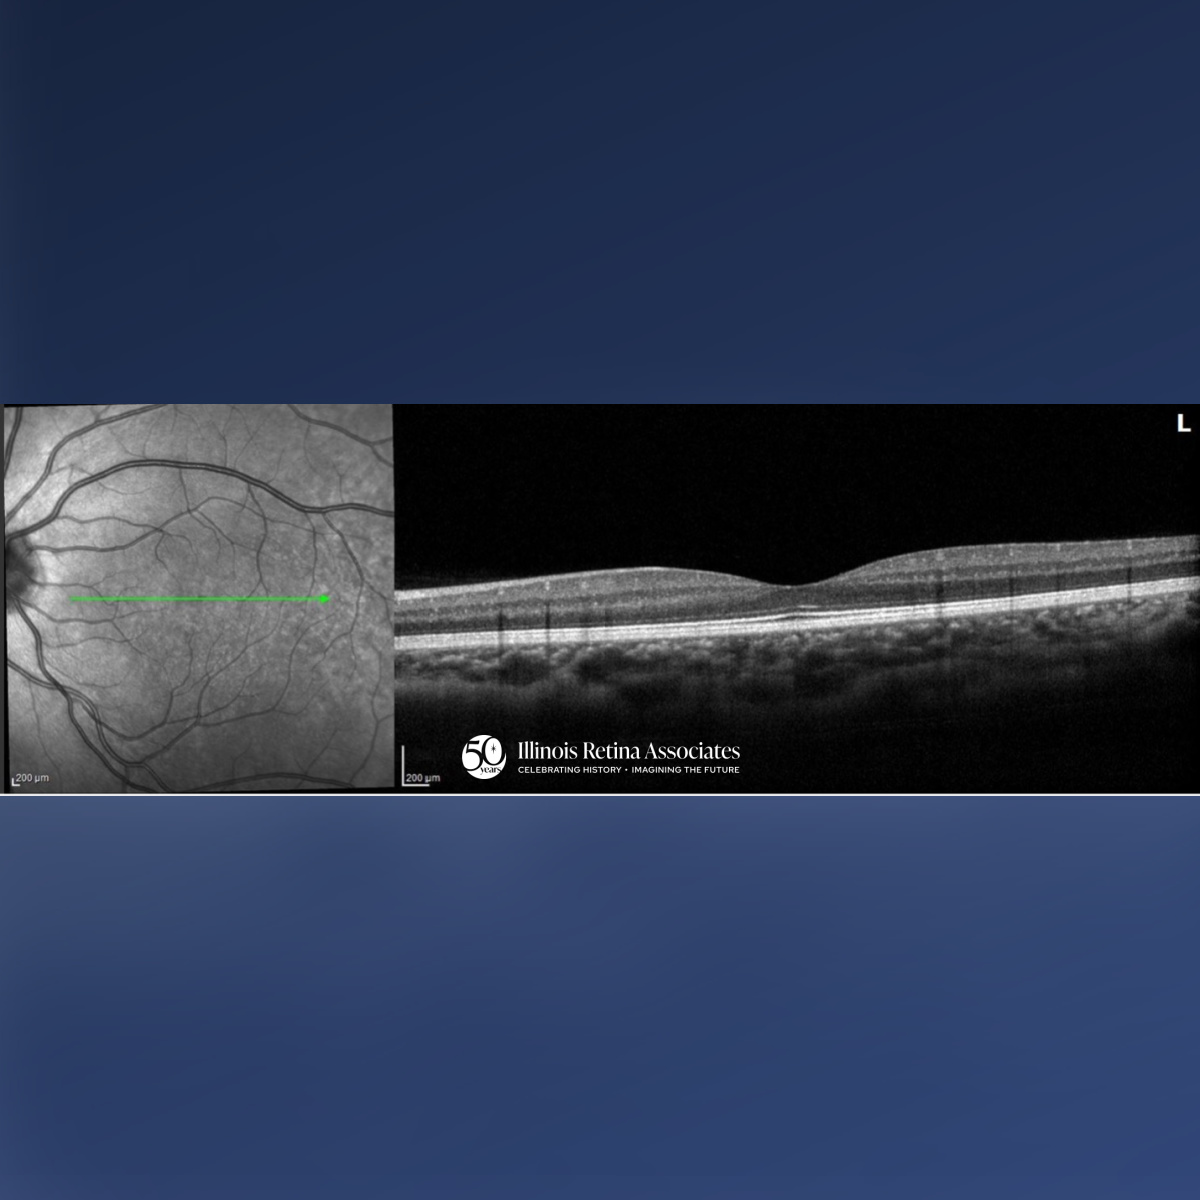

Visual acuity (VA) was 20/20 in both eyes (OU). Intraocular pressures and anterior segment exams were normal OU. Posterior segment exam OD demonstrated a cup to disc ratio (CDR) of 0.1 and a focal area of retinal whitening just superior to the fovea. Posterior segment in the left eye (OS) revealed a CDR of 0.1 and was otherwise unremarkable. Ocular Coherence Tomography (OCT) OD was significant for a band-like hyperreflectivity of the inner retinal layers (Fig 1) and FAF OD demonstrated mild hypo-autofluorescence overlying the area of retinal whitening (Fig 2). OCT OS was unremarkable (Fig 3). The patient was referred to the emergency department for a stroke evaluation which was negative. He returned approximately one week later where his VA remained stable at 20/20, and OCT showed slight improvement of the inner retinal hyperreflectivity (Fig 4). His central scotoma, however, remained unchanged.

PAMM is an ischemic macular disorder affecting the inner nuclear layer, often presenting with a sudden paracentral scotoma with minimal VA loss.1 PAMM can affect a wide-range of individuals from healthy patients to those with underlying systemic or retinal vascular disease, including arterial or venous occlusion, diabetes, or hypotension.2 Diagnosis is image-based: acute OCT imaging shows band-like hyperreflectivity of the inner nuclear layer, followed by focal thinning. FAF may be normal or show subtle hypo-autofluorescence. OCT-A can reveal capillary plexus flow deficits.3 While generally self-limited, paracentral scotomas may persist despite preserved visual acuity, reflecting permanent middle retinal ischemic injury.1